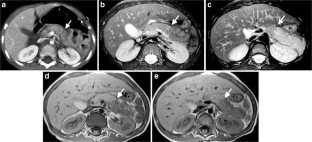

Of 3,265 patients presented as trauma team activations during the study period, only 28 (0.86%) children (19 boys, 9 girls; mean age: 7.14 years; age range: 1–15 years) had pancreatic injury. Of the available 27 CTs of the abdomen, 26 were performed on the day of trauma. Associated injuries were seen in 25/27 children, most frequently in the liver and lung, 16 (59.2%) each. There were 5 (19%) Grade I, 9 (33%) Grade II, 8 (30%) Grade III and 3 (11%) Grade IV. No patients had Grade V injury. No pancreatic parenchymal injury was identified in 2 (7%) patients with isolated fluid around the pancreas and mesentery. The pancreatic duct was visible in all 10 children (days: 0–330, median days: 41 post-trauma) who had MRI. Eight of these children, who had Grade III/IV injuries on CT and confirmed pancreatic duct injury on endoscopic retrograde cholangiopancreatography (ERCP) or surgery, showed either signal intensity difference in pancreatic parenchyma and/or caliber difference in the pancreatic duct proximal and distal to the injury site. Two patients died because of multiorgan injuries, 9 patients (mainly with Grade III and IV injuries) underwent surgery and/or ERCP, and 16 patients were managed conservatively. AAST grading of pancreatic injury on CT correlated with type of management (P=0.0001) with most of the Grade III and IV injuries treated with intervention and/or surgery while all of the Grade I and II injuries were treated conservatively.

Pancreatic injury is rare in children but often associated with other organ injuries most frequently involving the liver and lung. CT grading of injury correlates with management and guides intervention and/or surgery versus conservative treatment. MRI is useful for assessing pancreatic duct injury by demonstrating the pancreatic duct directly and/or secondary changes like signal intensity difference in pancreatic parenchyma and caliber difference in the pancreatic duct.